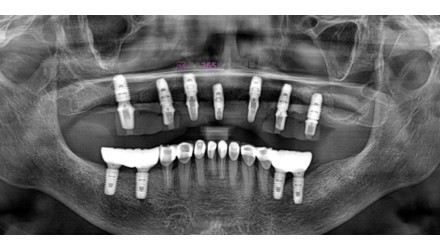

치료사례임플란트

박*수 임플란트 시술 사례

전체 임플란트

20**.**.**

치료 전

치료 후